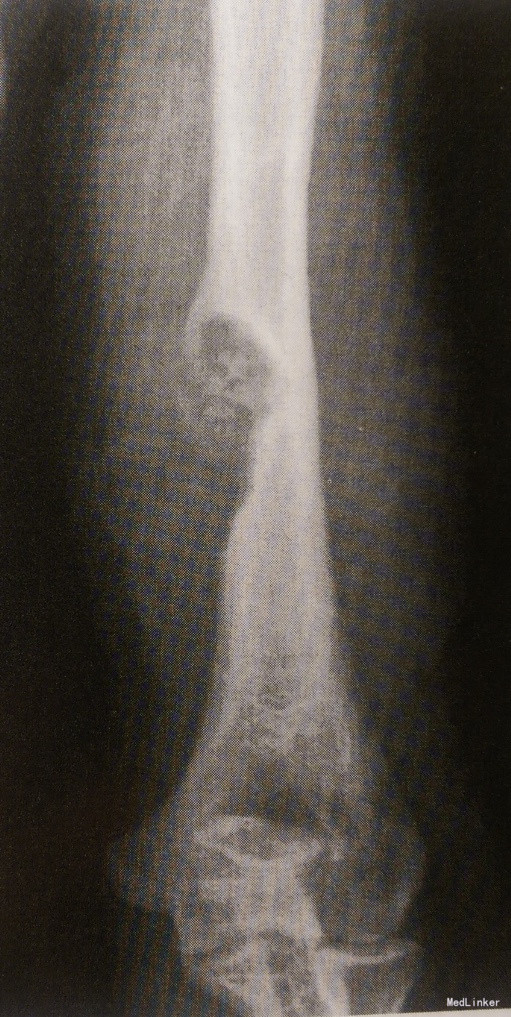

患者女,39岁,左上臂酸痛数年,发现上臂肿物一月余。

查体生命体征平稳,心肺腹体检无明显异常。 影像学检查:X线提示左肱骨中段内侧骨质破坏,破坏区髓腔侧有硬化缘,破坏区内见小斑片状钙化影、骨化影。MRI显示左肱骨后内侧骨皮质局限缺损,可见类圆形肿块,T1WI为等信号,T2WI为稍高信号,其内散在低信号灶,增强扫描肿块明显强化。

诊断:左肱骨骨母细胞瘤 治疗:手术治疗 病理:镜下见肿瘤由成骨细胞、骨样组织和骨组织组成,含有纤维性间质血管和散在的多核巨细胞。

此例为发生于长管状骨的骨母细胞瘤,相对较少,起源于骨皮质,呈偏心性膨胀生长,表现为左肱骨中段内侧的骨质破坏,破坏区髓腔侧有硬化缘,皮质膨胀变薄,X线平片可清晰显示破坏区内散在的斑片状钙化灶,具有特征性。